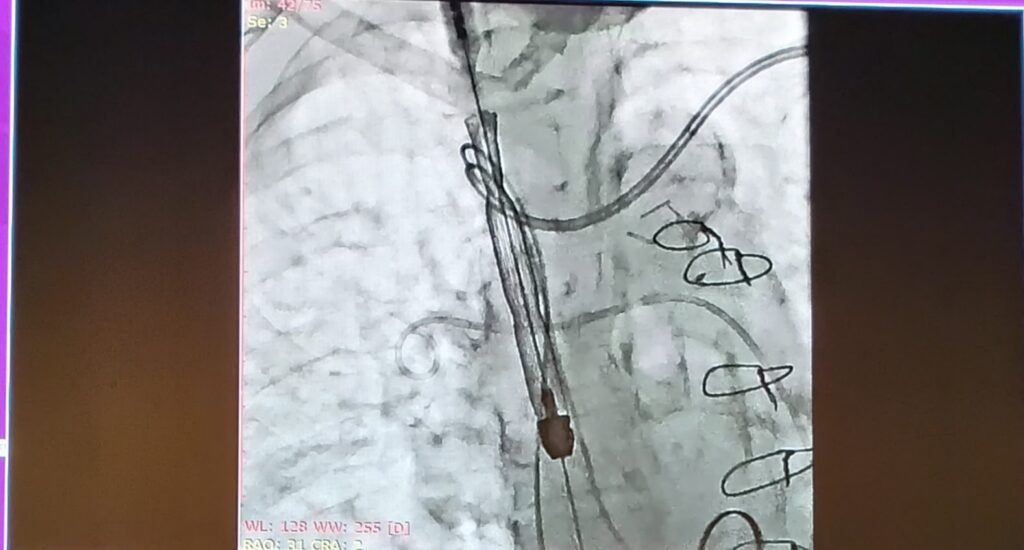

Surgical image from presentation at PCR Rio Valves 2025

P&F sponsored session Minimalist approach to tricuspid valve therapy,” highlighted the role of the TricValve® device in the management of tricuspid regurgitation. Clinical case presentations illustrated the feasibility of a minimally invasive, non-contrast, transthoracic echocardiography-guided approach for TricValve® implantation. The data emphasized procedural safety while demonstrating effective hemodynamic improvements. In addition, clinical outcomes were presented showing enhancements in patient quality of life, reductions in hospitalization rates, and decreases in right ventricular pressures following device implantation.